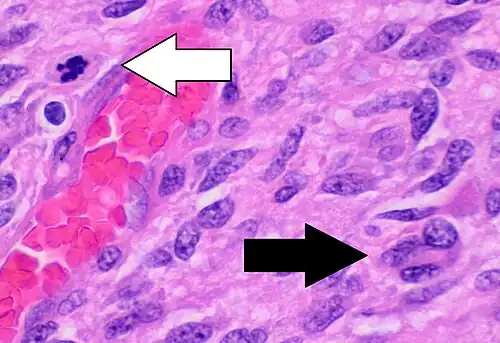

-

Histopathology of glioblastoma, showing high grade astrocytoma features of marked nuclear pleomorphism, multiple mitoses (one at white arrow) and multinucleated cells (one at black arrow), with cells having a patternless arrangement in a pink fibrillary background on H&E stain.

Histopathology of glioblastoma, showing high grade astrocytoma features of marked nuclear pleomorphism, multiple mitoses (one at white arrow) and multinucleated cells (one at black arrow), with cells having a patternless arrangement in a pink fibrillary background on H&E stain. -